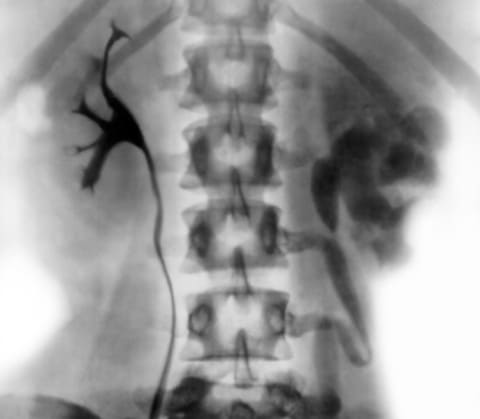

Кроме подтверждения диагноза, больному необходимо определить анатомическое и функциональное состояние почек. Это можно сделать с помощью ультразвукового исследования органов забрюшинного пространства и экскреторной урографии. Результаты данных методов полностью зависят от стадии заболевания. Если на начальных этапах может не быть вообще никаких изменений, то в поздние стадии отмечаются как структурные изменения, так и нарушения выделения мочи одной или двумя почками.

Экскреторная урография при туберкулезе почек